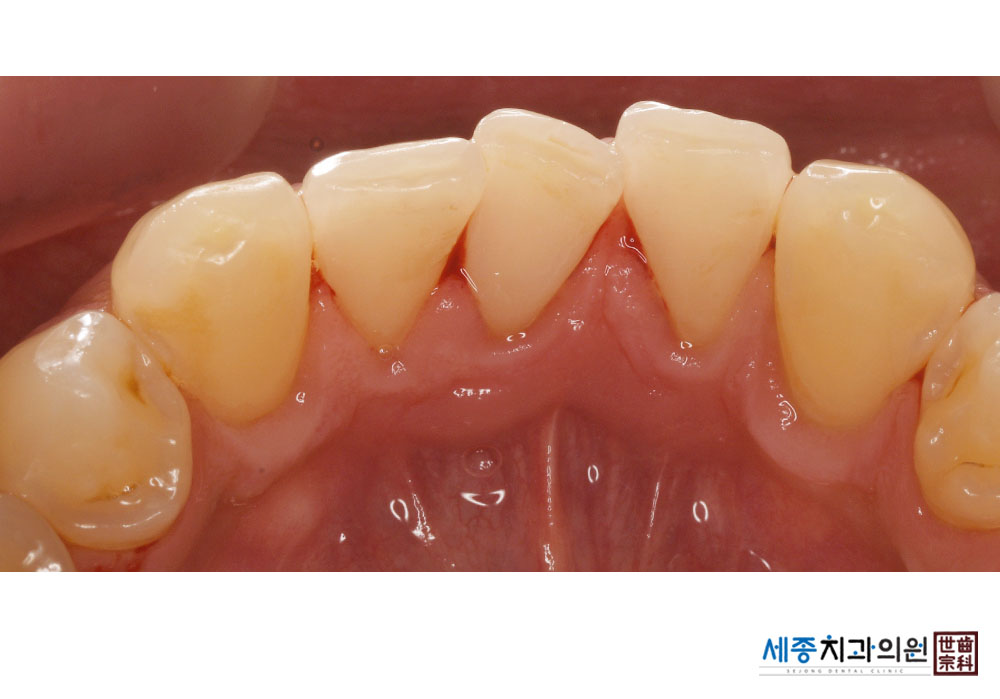

[스케일링] 치주질환 예방 스케일링

치료후 : 2022-08-22

가글마취&저주파 스켈러를 사용한 스케일링